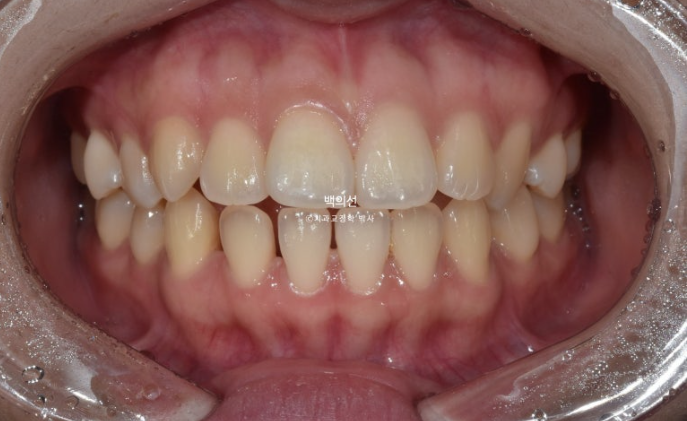

2년 전 인비절라인 교정치료를 위해 내원한 환자분입니다.

환자분이 고치고 싶은 것은

치아 비대칭

앞니로 면이 안 끊김 (개방교합)

두 가지입니다. 안모에서는 돌출입도 보였습니다.

23.01

앞니 중심선이 다르고 아랫니에 듬성듬성 공간이 벌어져 있습니다.